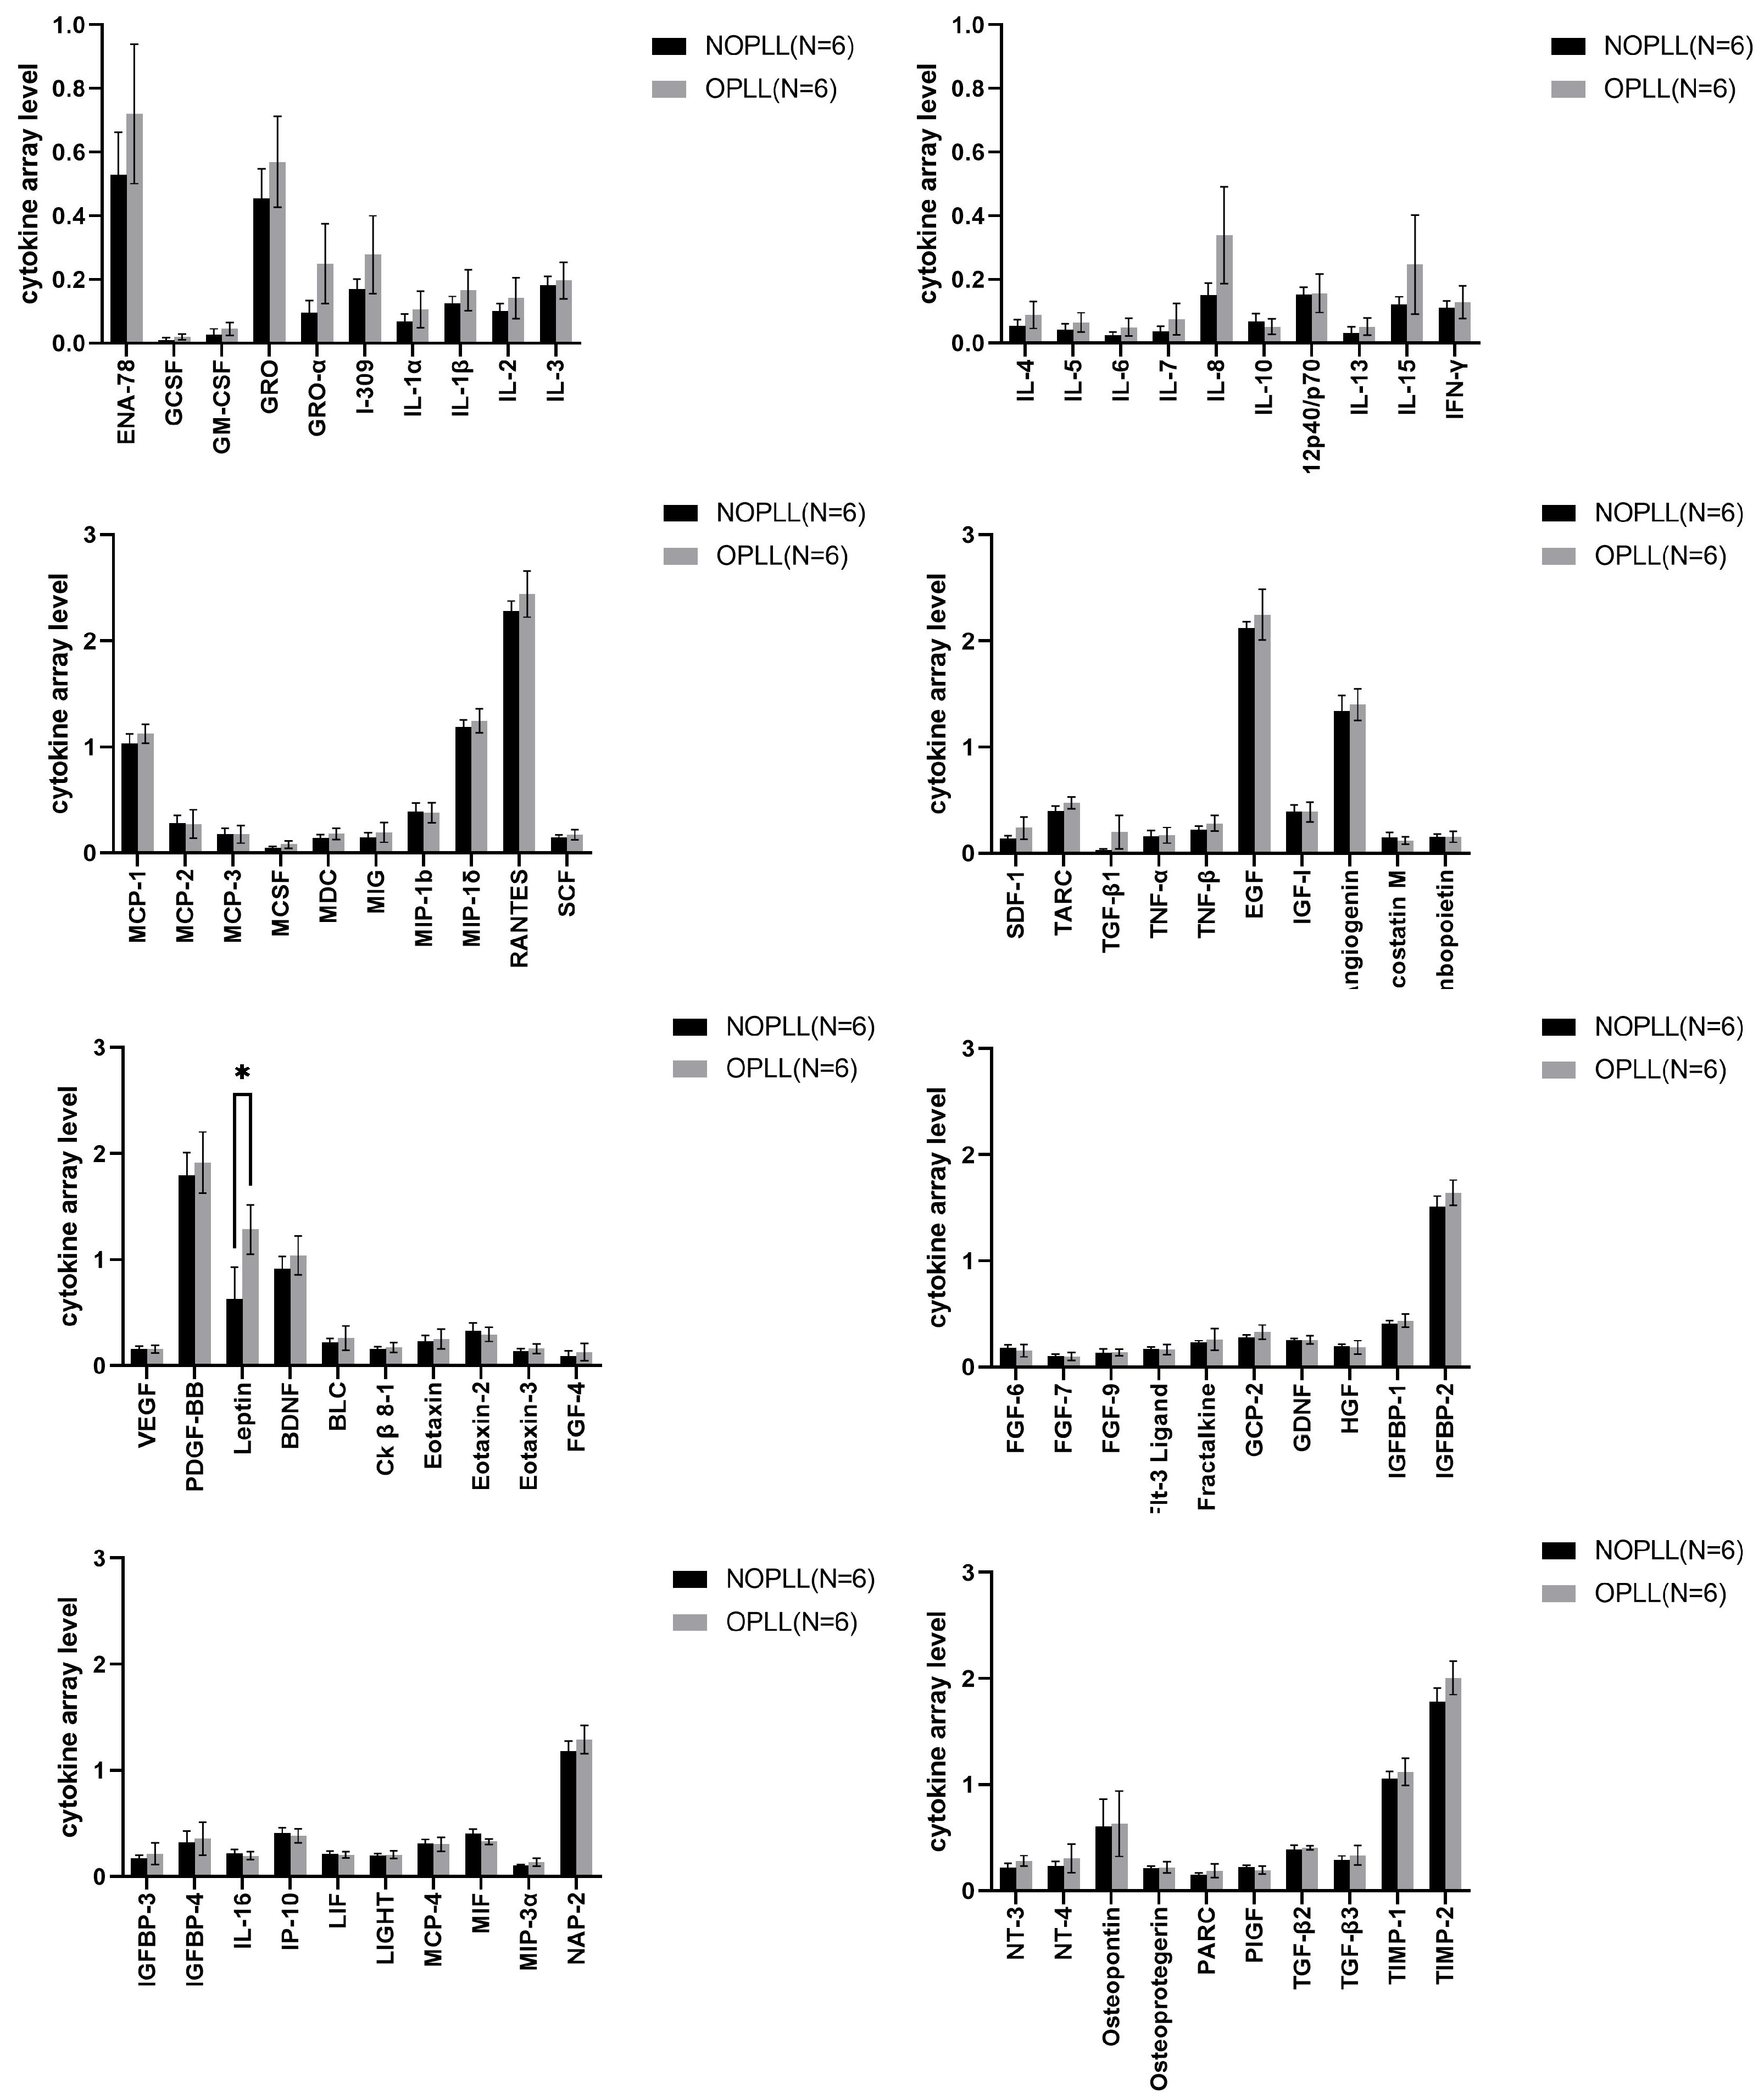

3.3. Serum Cytokine

3.5. Level of Proteins in OPLL vs. NOPLL

3.6. Levels of Proteins in Serum vs. Tissue: Serum/Tissue > 2

3.7. Levels of Proteins in Serum vs. Tissue: Tissue/Serum > 2

4.3. Leptin

4.4. Angiogenesis Factors: ANG, vEGF, and Osteopretegerin